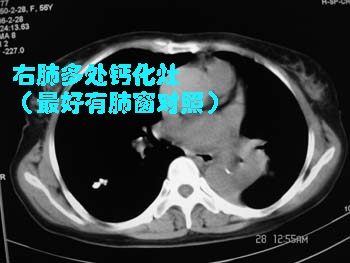

大家平时看肺都不看肺窗吗?

左侧胸廓容积缩小,纵隔左移,左下肺支气管闭塞.考虑中心型肺癌并左肺下叶不张,建议纤支镜.右肺及肺门区钙化灶,有下肺紧贴胸膜的小结节影

考虑中心型肺ca并左肺下叶肺不张。(应提供肺窗)